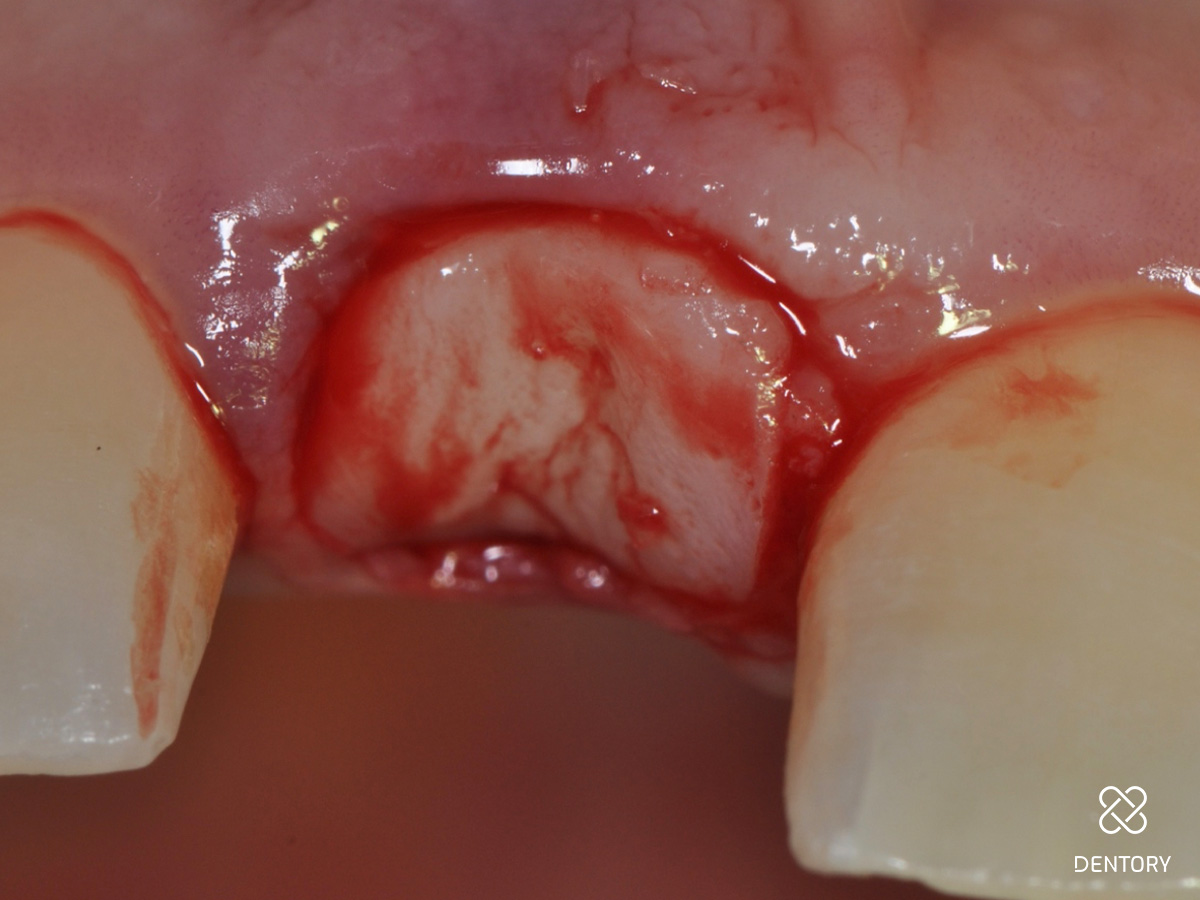

Abbildung 8

Das Saumepithel wurde entfernt und eine Blutung ausgelöst.